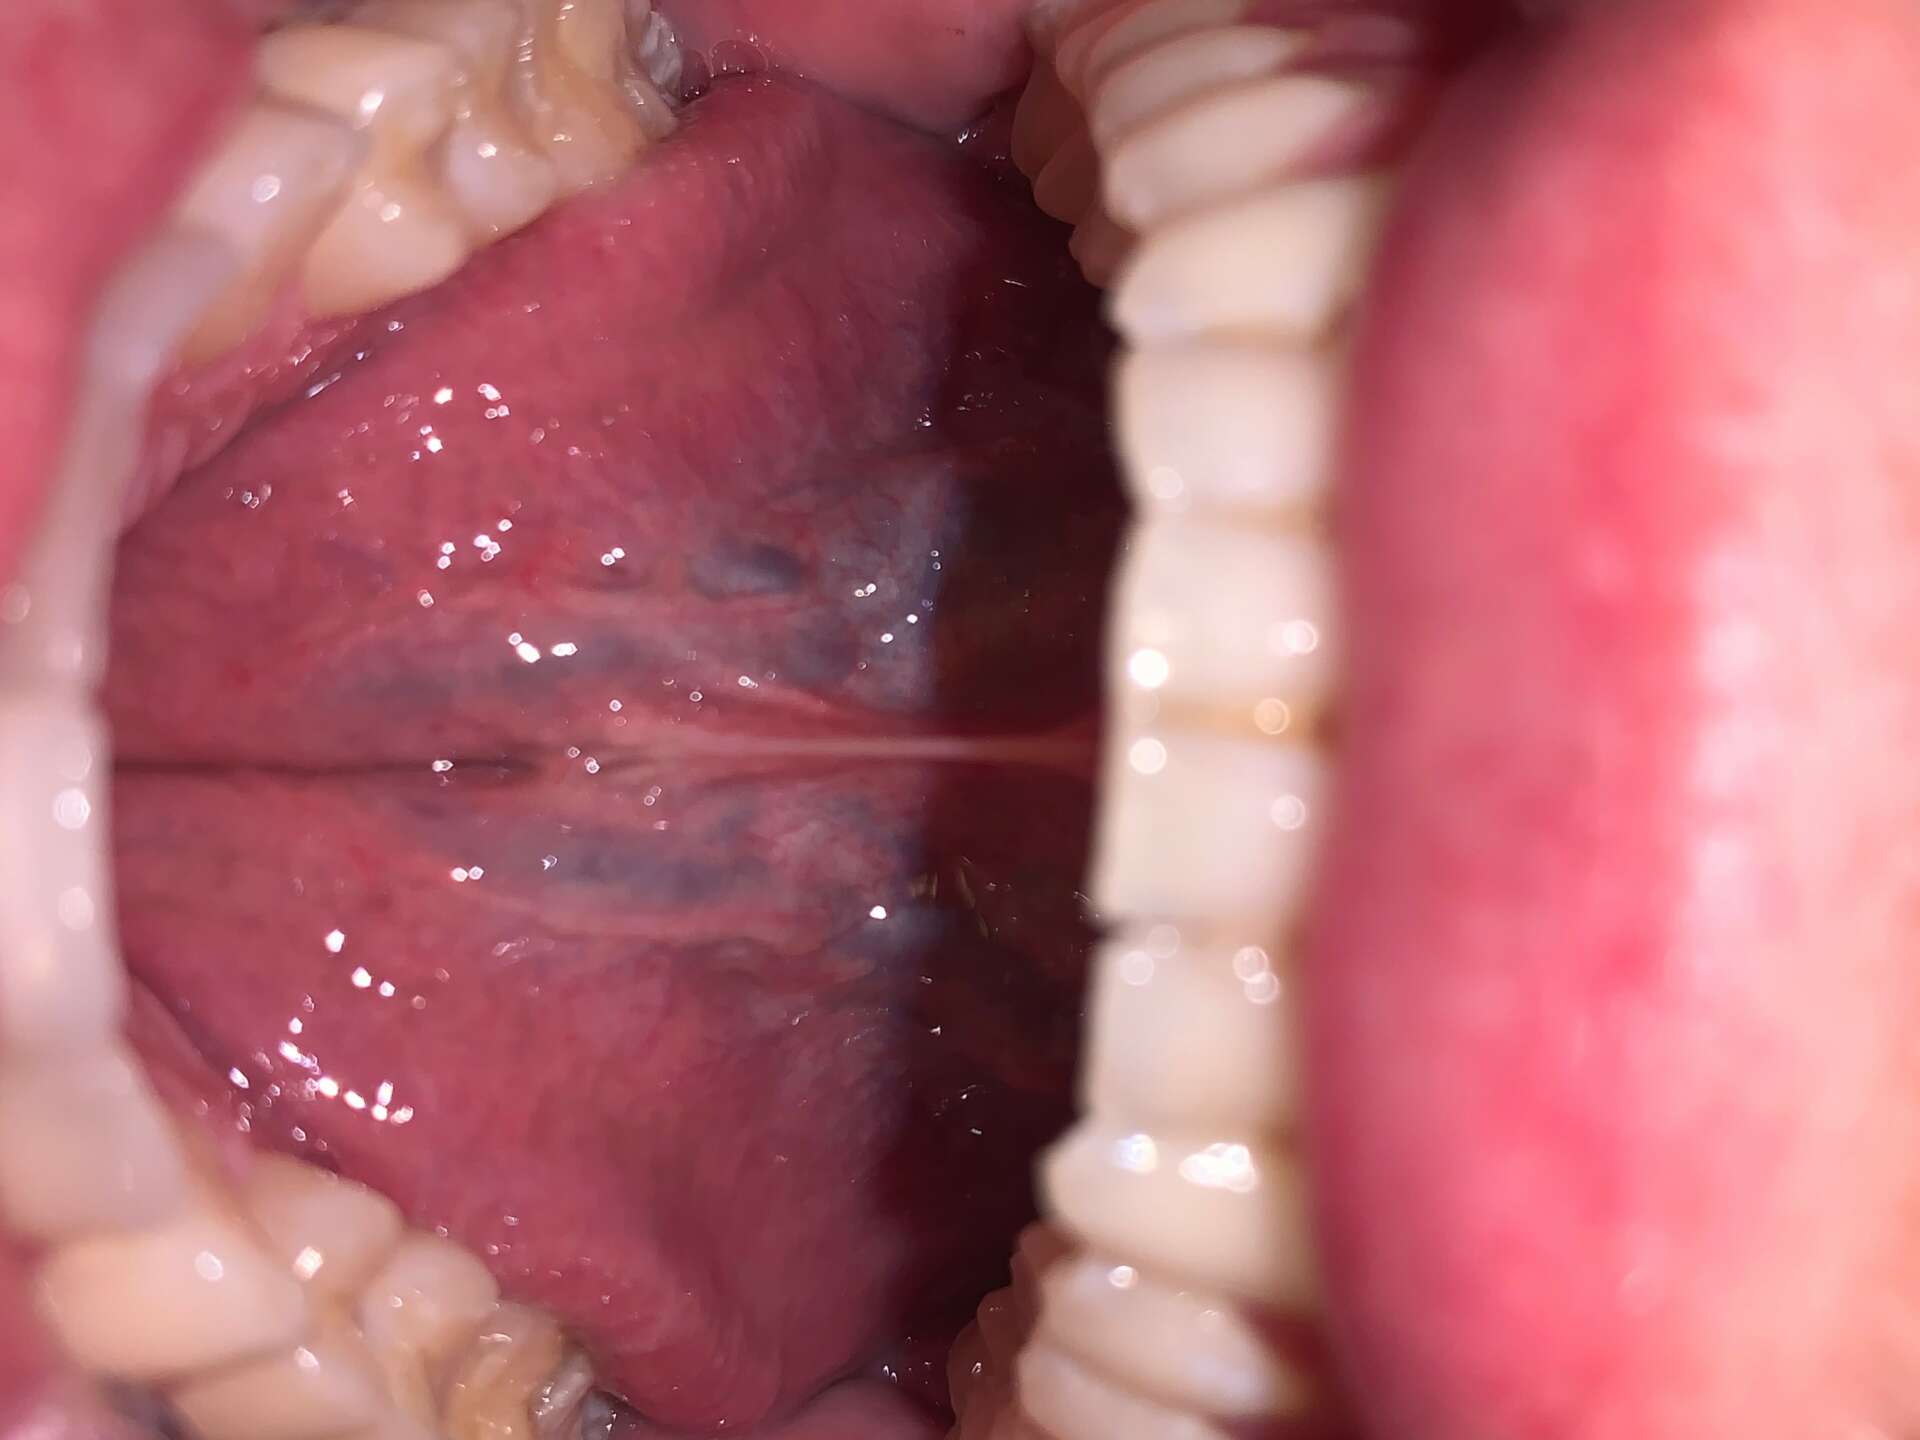

As a parent of two beautiful tongue tied children, I know the struggles first time moms can go through. Breastfeeding issues, “Colic”, reflux-like symptoms, sleep concerns, solid food issues are all things that people do not talk about enough. It has become my goal and mission with the practice to have access to care to all moms who need it. Whether it be with lactation support or oral tie support, we want to bridge the gap for those that are in need.

I started with just watching as infants were treated in the office for lip and tongue ties. Soon after that I began my journey learning about MyoFunctional disorders that were caused by lip, tongue or cheek ties. Slowly I started treating patients and understanding how something that is undiagnosed like tongue ties or oral dysfunction could cause life long issues.

My BIGGEST goal as the practice owner is to have access to care. Assessing oral ties is our speciality in the practice. The symptoms that we work with mostly in the practice are: feeding issues (breast or bottle), mouth breathing, tonsil and adenoid issues, recurrent ear infections, speech issues, snoring or sleep apnea issues, TMJ pain, crowding of teeth and much more.

Photos of ties of my family and stock photo of tongue thrust photo.